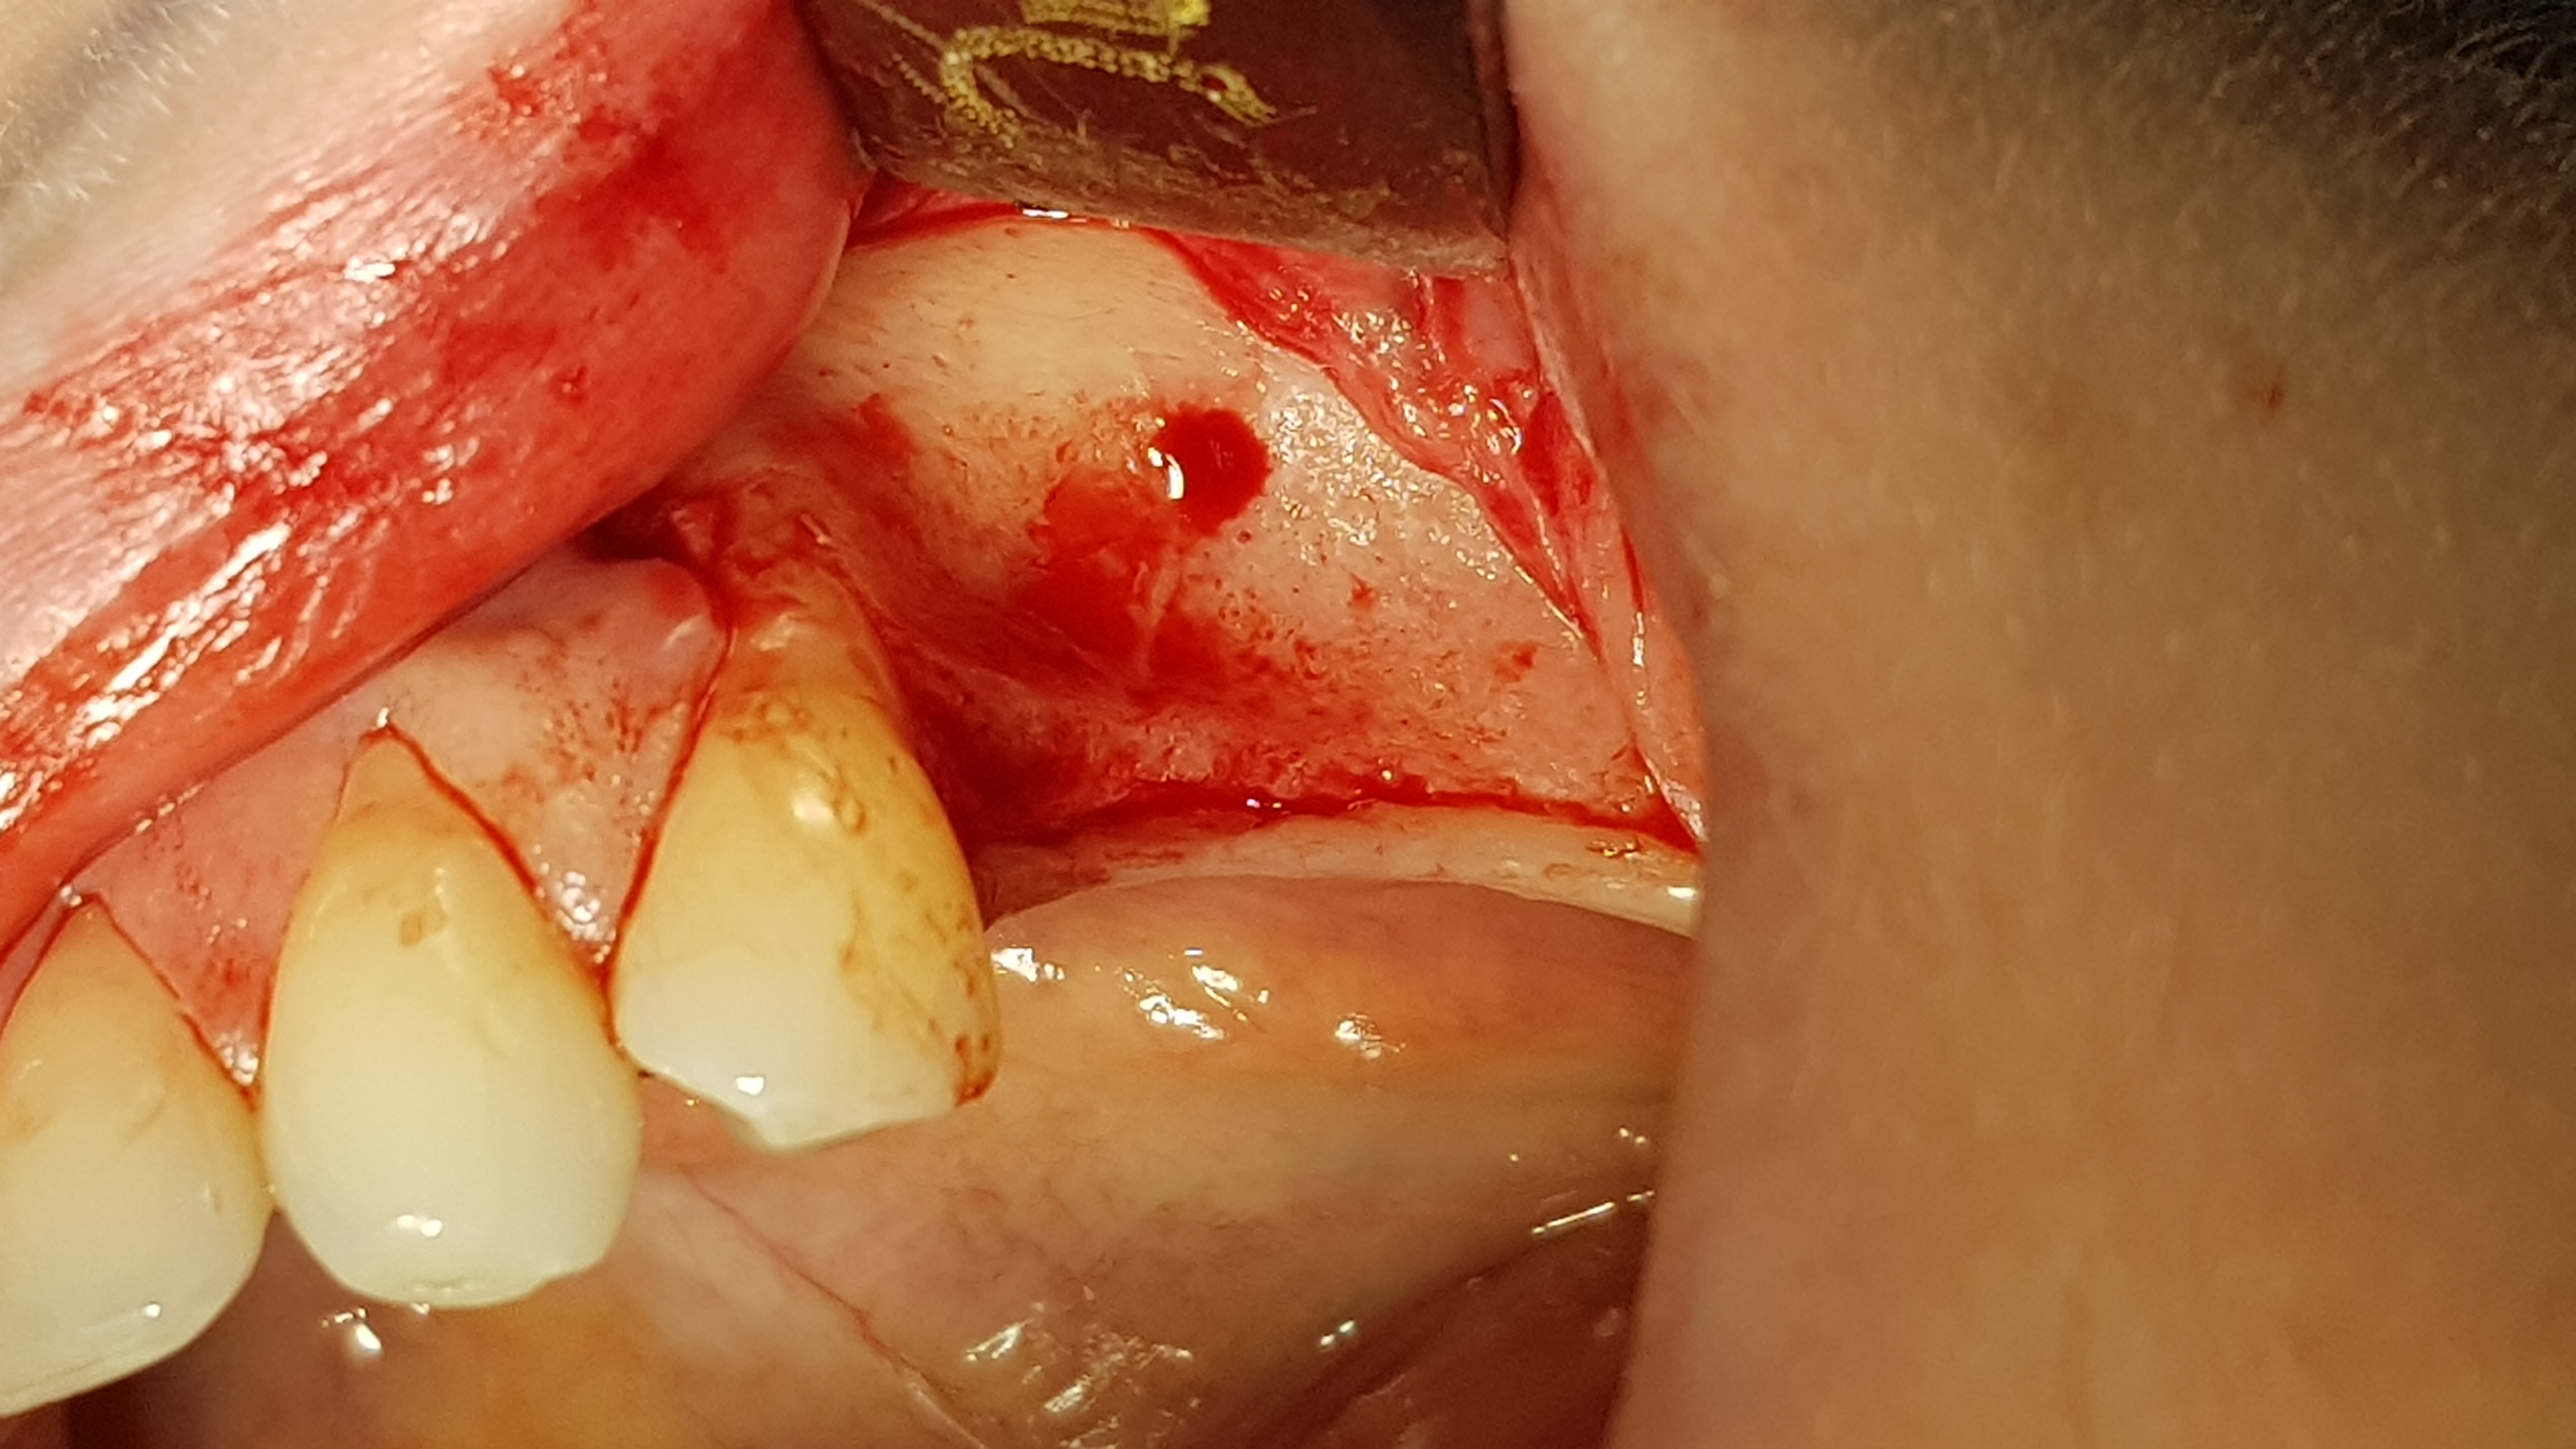

Brzegi rany zbliżono na odległość około 5 mm i zaopatrzono szwami (polidioksanon 4-0, igła okrągła kłująca, długość 16 mm, profil ½ koła). Po okresie 14 dni uzyskano ziarninowanie tkanki miękkiej. Drugi etap wykonano po 3 miesiącach. Dostęp do wyrostka wykonano w sposób typowy, jednym cięciem poziomym rozpoczynając na jego szczycie od okolicy 47, przedłużając do okolicy zęba 44 a następnie do przodu przez dziąsło zbite 44 i kończąc cięciem pionowym w połowie szerokości korony 44. Po odpreparowaniu tkanek miękkich uwidoczniono kość części zębodołowej, której powierzchnię poddano usunięciu pozostałości tkanek miękkich przy użyciu dedykowanych przez producenta wierteł z nasypem diamentowym.

Ryc. 6. Wytworzenie płata kątowego. Ryc. 7. Dekortykacja blaszki korowej.

Następnie wykonano otwory trepanacyjne w blaszce korowej kości o średnicy około 3 mm dochodząc do kości gąbczastej (ryc. 7). Taka średnica jest zalecana przez producenta dla lepszej retencji i utrzymania kształtu cementu regeneracyjnego w takim ubytku. Następnie po aktywacji umieszczono i uformowano cement na przygotowanej powierzchni kości (2 cm3) (ryc. 8).